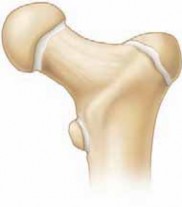

Precision Proximal Femoral Varus Osteotomy Using a 90-Degree Blade Plate

Chapter 27 Proximal Femoral Varus Osteotomy Using a 90-Degree Blade Plate Tom F. Novacheck DEFINITION Proxima…